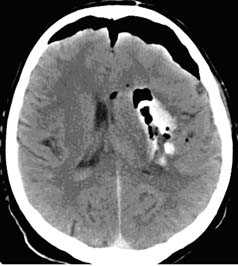

Методом выбора при диагностике ушиба головного мозга является КТ головного мозга. На КТ определяют ограниченную зону пониженной плотности, возможны переломы костей свода черепа, субарахноидальное кровоизлияние. При ушибе мозга средней степени тяжести на КТ или спиральной КТ в большинстве случаев выявляют очаговые изменения (некомпактно расположенные зоны пониженной плотности с небольшими участками повышенной плотности).

При ушибе тяжелой степени на КТ определяются зоны неоднородного повышения плотности (чередование участков повышенной и пониженной плотности). Перифокальный отек головного мозга сильно выражен. Формируется гиподенсивная дорожка в область ближайшего отдела бокового желудочка. Через нее происходит сброс жидкости с продуктами распада крови и мозговой ткани.

На КТ определяют двояковыпуклую, реже плоско-выпуклую ограниченною зону повышенной плотности, которая примыкает к своду черепа и локализируется в пределах одной или двух долей. Однако, если источников кровотечения несколько, зона повышенной плотности может быть значительного размера и иметь серповидной форму.

Обязательным методом обследования пострадавших с черепно-мозговой травмой является компьютерная томография. Относительными противопоказаниями к ее проведению могут служить геморрагический или травматический шок, а также нестабильная гемодинамика. С помощью КТ определяют патологический очаг и его расположение, количество и объем гипер- и гиподенсивных зон, положение и степень смещения срединных структур головного мозга, состояние и степень повреждения головного мозга и черепа.